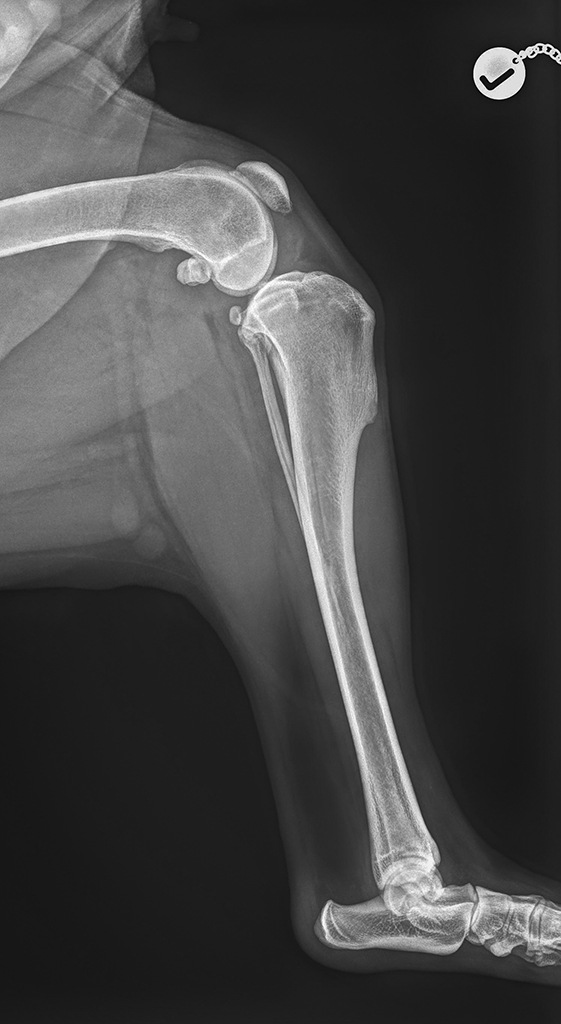

Die vermutete Diagnose wird röntgenologisch bestätigt (Gelenkfüllung, Schublade/Subluxation, typische Muster der Arthrose) und nur in seltenen Fällen ist aufwändigere Diagnostik zusätzlich notwendig (MRT, Arthroskopie, Gelenkpunktion).

Kreuzbandriss (Ruptur des vorderen Kreuzbandes) ist eine der häufigsten Ursachen für die Hinterbeinlahmheit beim Hund. Anders als bei Menschen, wo meistens ein akutes Trauma (Sturz, Sportverletzung) der Auslöser ist, steckt beim Hund in den meisten Fällen eine chronische degenerative Veränderung der Kreuzbandfasern dahinter. Anfangs lassen einzelne Fasern nach. Es kommt zu Entzündung im Kniegelenk mit minimaler Instabilität und weniger ausgeprägten Beschwerden. Wenn solche Patienten noch in dieser Phase nicht operiert werden, früher oder später (Wochen oder Monate) kommt durch das Nachlassen der restlichen Kreuzbandfasern zu einem kompletten Kreuzbandriss und Verschlechterung des Gangbildes.

Als Operationsmethode der Wahl für Hunde und Katzen aller Größen hat sich bei uns die sogenannte TPLO (Tibial Plateau Leveling Osteotomy) Operation etabliert. Diese Methode ermöglicht dynamische Stabilisation und ist auch nach eventueller Entfernung der Implantate unverändert wirksam.